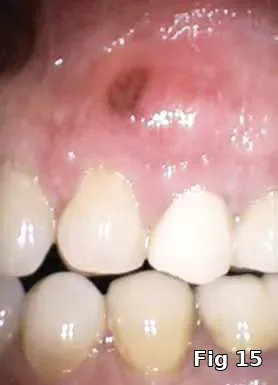

Ridge preservation — use as a membrane: Here is a 40-year-old male who presented for the evaluation of a painful swelling in his gum (Fig. 15). Diagnosis was peri-apical abscess with sinus fistula, possible midroot fracture of tooth #13 (Fig. 16) and a treatment plan to extract the tooth (Fig. 17) and ridge preserve followed by implant placement and an implant-supported fixed restoration.